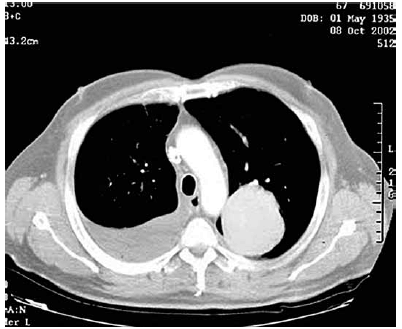

Paciente do sexo masculino, 45 anos, procura ambulatório de clínica médica relatando que há dois meses iniciou quadro de dor em hemitórax direito que piorava com a inspiração profunda. Essa dor diminuiu gradualmente ao mesmo tempo que surgiram episódios de febre baixa (37,9 oC) sempre no final da tarde. Relata emagrecimento de 9 kg nesse período. Tabagista 40 anos/maço. Nega antecedentes mórbidos pessoais ou contato com pessoas doentes. Após exame físico, o médico solicita uma tomografia computadorizada de tórax que está apresentada a seguir.

A principal hipótese diagnóstica é: